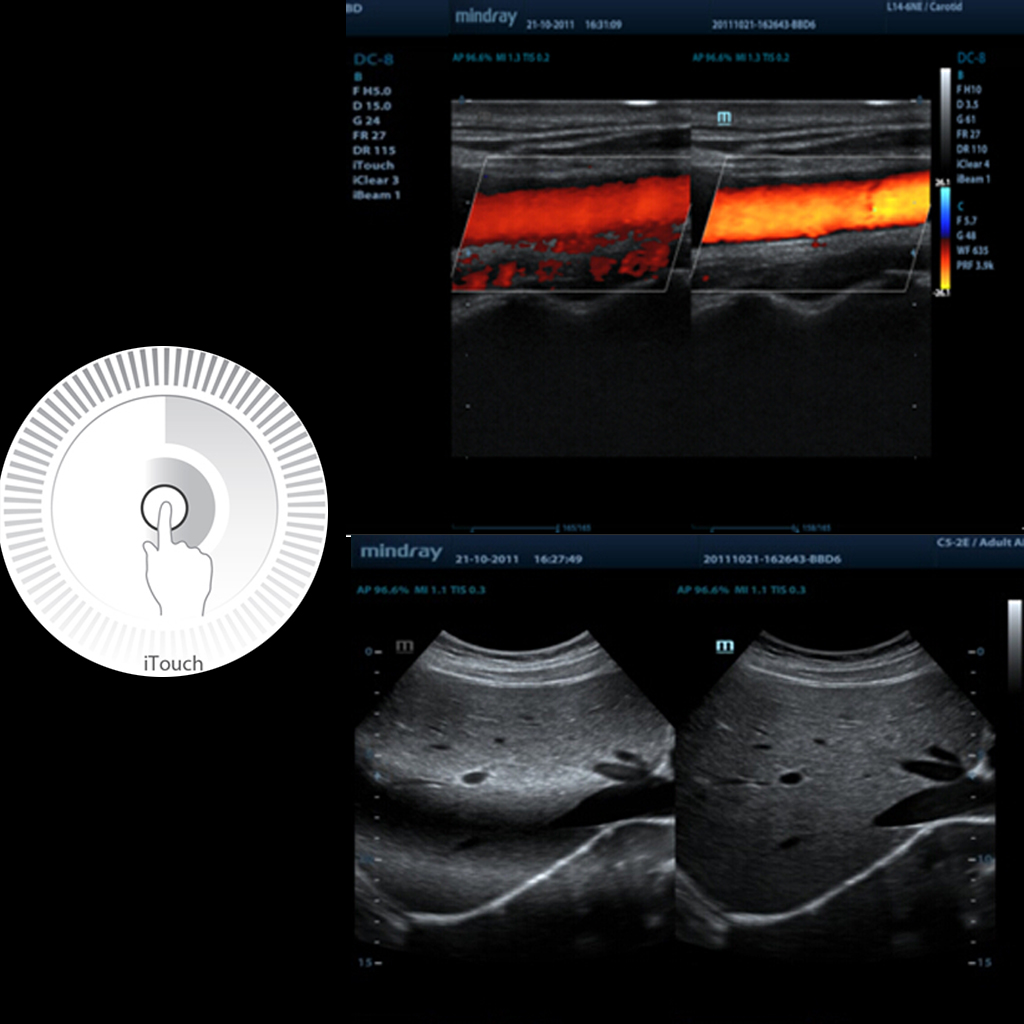

iTouch™ - Софтуер за ветеринарен ехограф Mindray